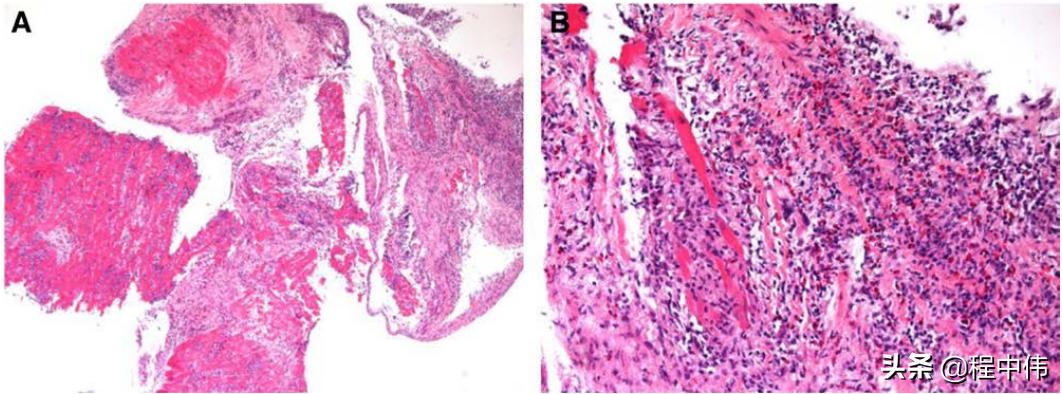

坏死性嗜酸粒细胞心肌炎病理示例见下图,